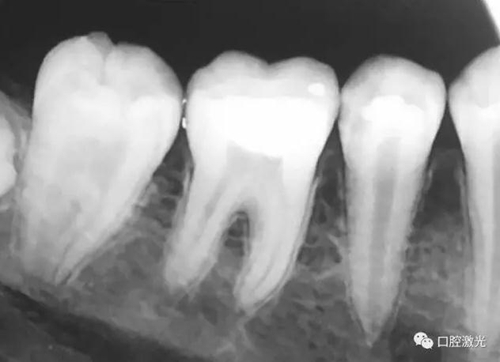

活髓理療治療結(jié)果令人滿意,沒有出血,也沒有出現(xiàn)碳化。患者沒有感受到不適并表示滿意。為了跟蹤激光輔助活髓切除術(shù)的治療效果,手術(shù)完成即刻和5周后分別拍攝了X光圖像。5周后的牙髓活性溫度測(cè)試也顯示陽性。

治療后即刻